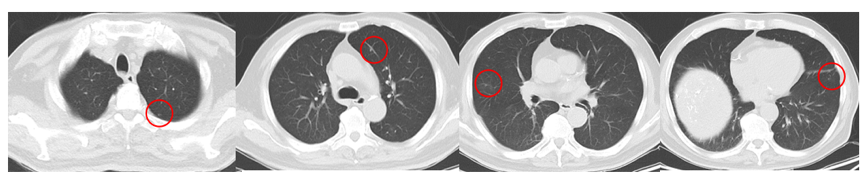

2021年3月8日复查AFP为>1210ng/ml;2021年3月8日复查CT提示,双肺转移双侧肾上腺转移;左侧肾上腺较前变小,但右侧肾上腺明显增大;右侧髂骨转移(图5)。

图5.2021年3月8日复查CT

2022年2月8日复查CT提示,肺部病灶基本消失(图11),肾上腺病灶明显缩小,髂骨病灶进一步退缩(图12)。2022年2月9日AFP为411ng/ml。

图11.2022年2月8日复查胸部CT

图12.2022年2月8日复查CT